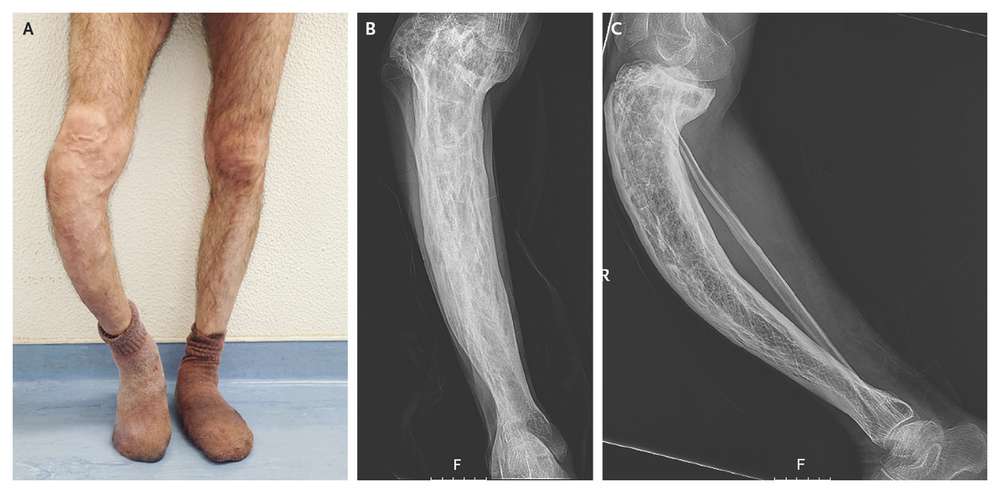

Physical examination revealed a prominent saber-like tibia and superficial venous circulation related to chronic venous insufficiency (image below, Panel A). Radiographs showed cortical thickening, trabecular enlargement, and bowing of the tibia (Panel B shows the anteroposterior view and Panel C the lateral view).

Levels of bone turnover markers were increased, including an alkaline phosphatase level of 345 U per liter (normal range, 45 to 129), an N-terminal propeptide of type I procollagen (P1NP) level of 506.3 ng per milliliter (normal value, <36.4), and a level of the β-isomer of the C-terminal telopeptide of type I collagen (β-CTX) of 1.38 ng per milliliter (normal value, <0.30). These findings show the clinical sequelae of prolonged early-onset Paget’s disease of bone.